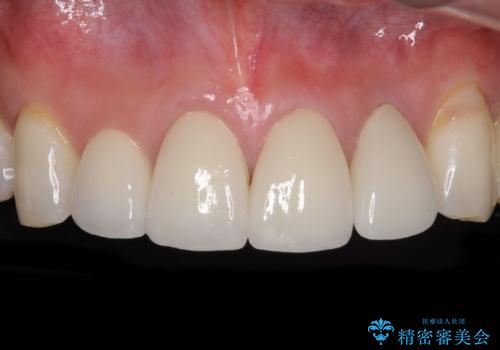

目立つ範囲である前歯4歯をオールセラミッククラウンにて補綴することとしました。

口元の印象が明るくなり、人前で気にせずに笑えるようになりました。